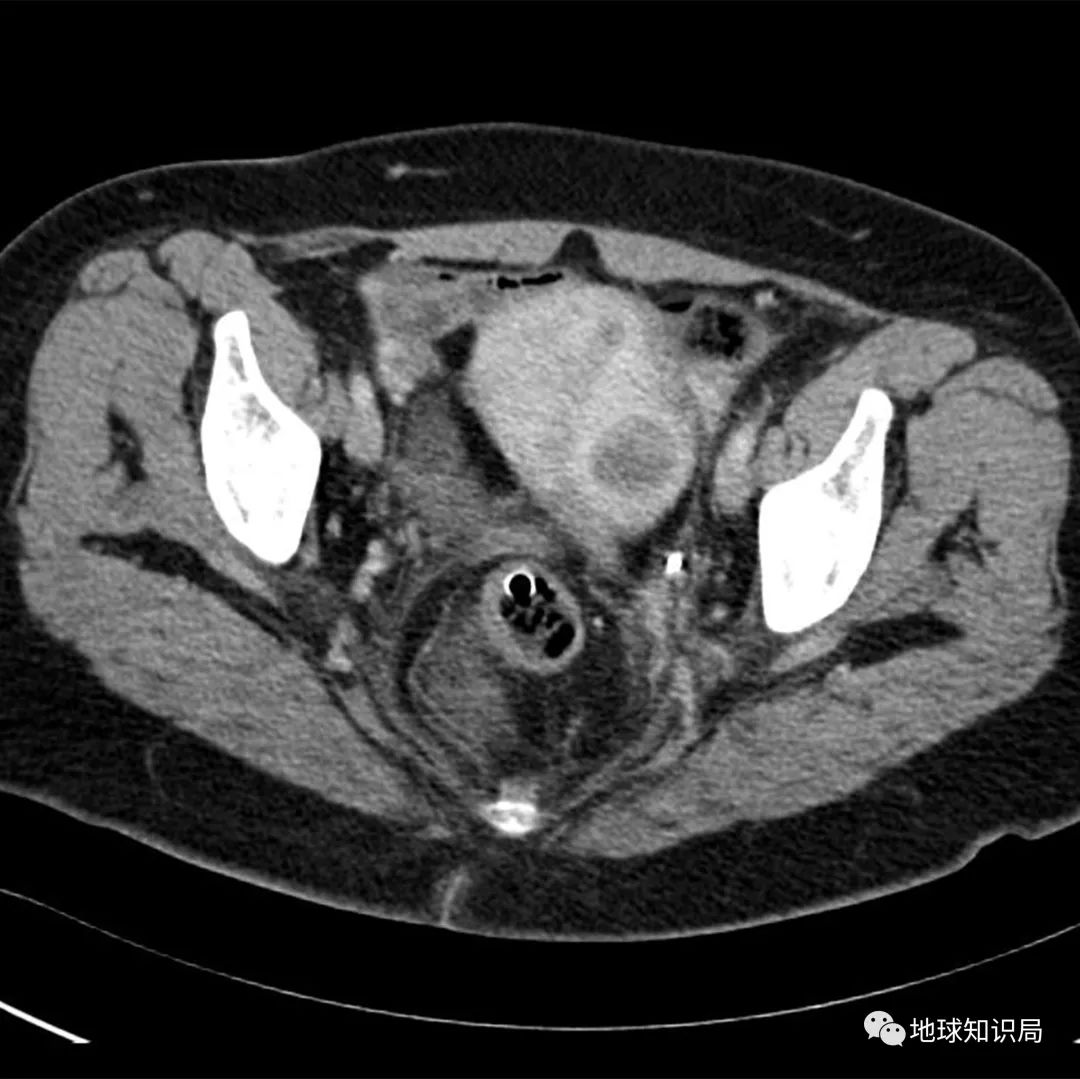

目前临床上子宫切除术需要严格掌握适应症与禁忌症, 适应症 包括:较大的子宫良性肿瘤;恶性肿瘤;子宫腺肌病、子宫内膜异位症等,且保守治疗无效;子宫脱垂、子宫翻出、子宫破裂等,且不需要或不能保留子宫。

(子宫肌瘤的CAT扫描 图:wiki)▼